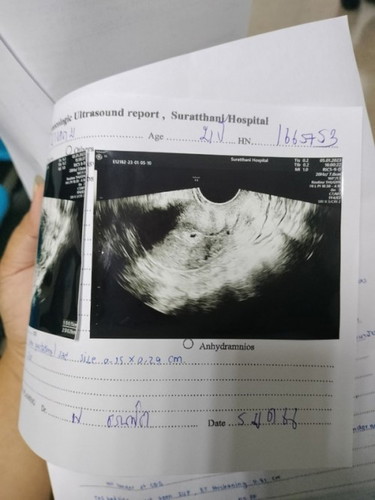

มีใครเคยตรวจครรภ์ตอน5สัปดาห์บ้างคะแล้วไม่เจอตัวเด็กถุงการตั้งครรภ์ก็เล็กมากหมอ บอกว่า5สัปดาห์ถุงการตั้งครรภ์น่าจะใหญ่กว่านี้เสี่ยงเป็นท้องลมมากกังวลมากๆเลยค่ะไม่อยากให้ท้องลมเลยมีใครเป็นแบบนี้แล้วมาตรวจใหม่เจอตัวเด็กบ้างคะอีก2สัปดาห์มาซาวด์ใหม่หวังเล็กๆว่าให้เจอตัวเด็ก #ของเค้าซาวด์ทางช่องคลอดนะคะ